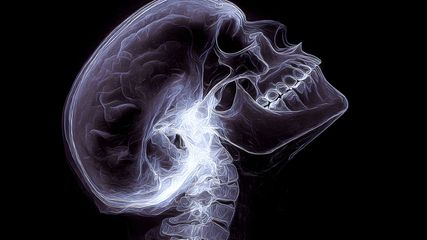

Alle diese Beschwerden werden häufig in der Allgemeinarztpraxis genannt und können die verschiedensten Ursachen haben. Vorliegender Artikel soll für die Beachtung des Zusammenhangs der genannten Symptome aus Tabelle 2 mit Funktionsstörungen im Bereich des Kiefergelenks sensibilisieren. Hinweisgebend ist die Klage der Patient:innen über eine verspannte Kaumuskulatur nach dem morgendlichen Erwachen, manchmal auch Ohrenschmerzen. Die Patient:innen streichen intuitiv die Kiefermuskulatur aus und beklagen auf Nachfrage Schmerzen und Verspannungen in diesem Bereich. Der M. masseter ist dann bei Palpation empfindlich. Manchmal ist ein Gelenkkrepitus bei Öffnung des Kiefergelenks zu hören oder die Mundöffnung ist vermindert. Die normale Mundöffnung beträgt 3 Querfingerbreiten in Längsrichtung (Abb. 1). Bei Ausschluss von Pathologien im HNO-Bereich sind diese Symptome verdächtig auf Kiefergelenkstörungen.3